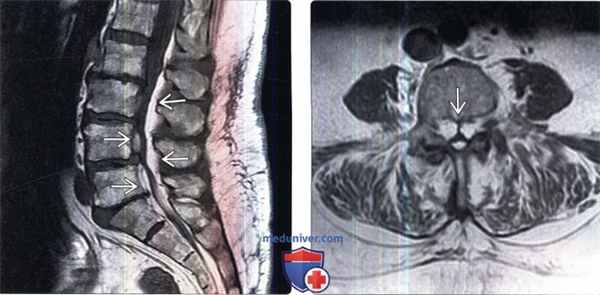

МРТ грудного отдела без контрастирования:

- кифосколиотическая деформация

- краевые костные разрастания тел позвонков

- дегенерация желатинозных ядер и уменьшение Т2-сигнала от дисков

- высота тел Th4, Th5, Th6, Th7, Th8, Th11, Th12 снижена

- в телах - участки с гиперинтенсивным сигналом на Th1 и Th2

- узурация замыкательных пластин тел Th4-Th12 с формированием множественных грыж Шморли

- изменение сигнала в T1, Т2, STIR от тел Th7 и Th 8 позвонков

- повышение сигнала в Т2 от диска Th7-8

- медианная грыжа Th7-8 до 3 мм, умеренно деформирующая дуральный мешок и суживающая просвет позвоночного канала на данном уровне

- на уровне Th4-Th9 в задних отделах канала - экстрамедуллярное скопление жировой ткани: картина эпидурального липоматоза с деформацией дурального мешка, с сужением субарахноидального пространства, с воздействием на спинной мозг на уровне Th6-Th8 и уменьшением диаметра спинного мозга (атрофические изменения) на данном уровне

- повышение сигнала от спинного мозга на уровне Th4-Th9 (миелоишемия? миелит?)

- заключение: картина может соответствовать спондилодисциту Th7-Th8; признаки эпидурального липоматоза с деформацией дурального мешка и компрессией спинного мозга; изменения спинного мозга на уровне Th4-Th9 (миелоишемия? миелит?); деформация тел Th4-Th12 позвонков более характерна для изменений при гормональной спондилопатии; дегенеративно-дистрофические изменения грудного отдела, множественные грыжи Шморли, грыжа диска Th7-8.

(Слева) Сагиттальный срез, Т1-ВИ: гипертрофия эпидуральной клетчатки в дорзальном и вентральном отделе спинномозгового канала. Дуральный мешок уменьшен в передне-заднем направлении вследствие сдавления жировой тканью.

(Справа) На аксиальном Т1-ВИ определяются признаки выраженной гипертрофии эпидуральной клетчатки в поясничном отделе спинномозгового канала. Клетчатка в значительной степени сдавливает дуральный мешок, который принимает форму трилистника. Гипертрофированная клетчатка позволяет нам хорошо видеть связку Хоффмана, соединяющую заднюю продольную связку с вентральной поверхностью твердой мозговой оболочки.